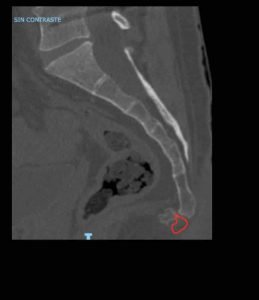

Caso real clínico: Luxación coxis

Paciente de 40 años intervenido previamente de artrodesis lumbar L4-L5 hace 4 años. Hace 18 meses sufrió caída de bicicleta y presentó fractura de coxis. El tratamiento de la fractura fue conservador. Paciente actualmente no tolera más de 10 minutos sentado.

TAC: corte de coxis luxado, en rojo donde debería estar el coxis.

Nuestro equipo realizó al paciente una radiofrecuencia del ganglio impar, y en el mismo acto quirúrgico se comprobó si el coxis era reducible (es decir si volvía a su sitio). Actualmente con el tratamiento proporcionado ha mejorado su calidad de vida y tolera estar sentado hasta 2 horas. Este es el vídeo del caso: